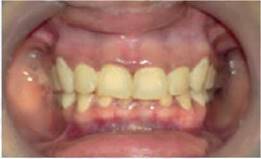

Examen físico: se realiza exploración de macizo facial y cuello donde se observa fascie terrosa con ligera pigmentación violácea perilabial; intraoralmente llama la atención pigmentación en ribete gingival inferior de color violáceo (Figura 1). Destaca además en palmas de manos, plantas de pies y uñas coloración azul oscuro e hiperpigmentación periungueal (Figura 2). Por las características clínicas, sitios anatómicos de pigmentación y signos y síntomas de la paciente, se presume enfermedad endocrino-metabólica, muy subjetiva a enfermedad de Addison, por lo que se remite a valoración por especialidad de Endocrinología.

Figura 1: Hiperpigmentación en mucosa oral